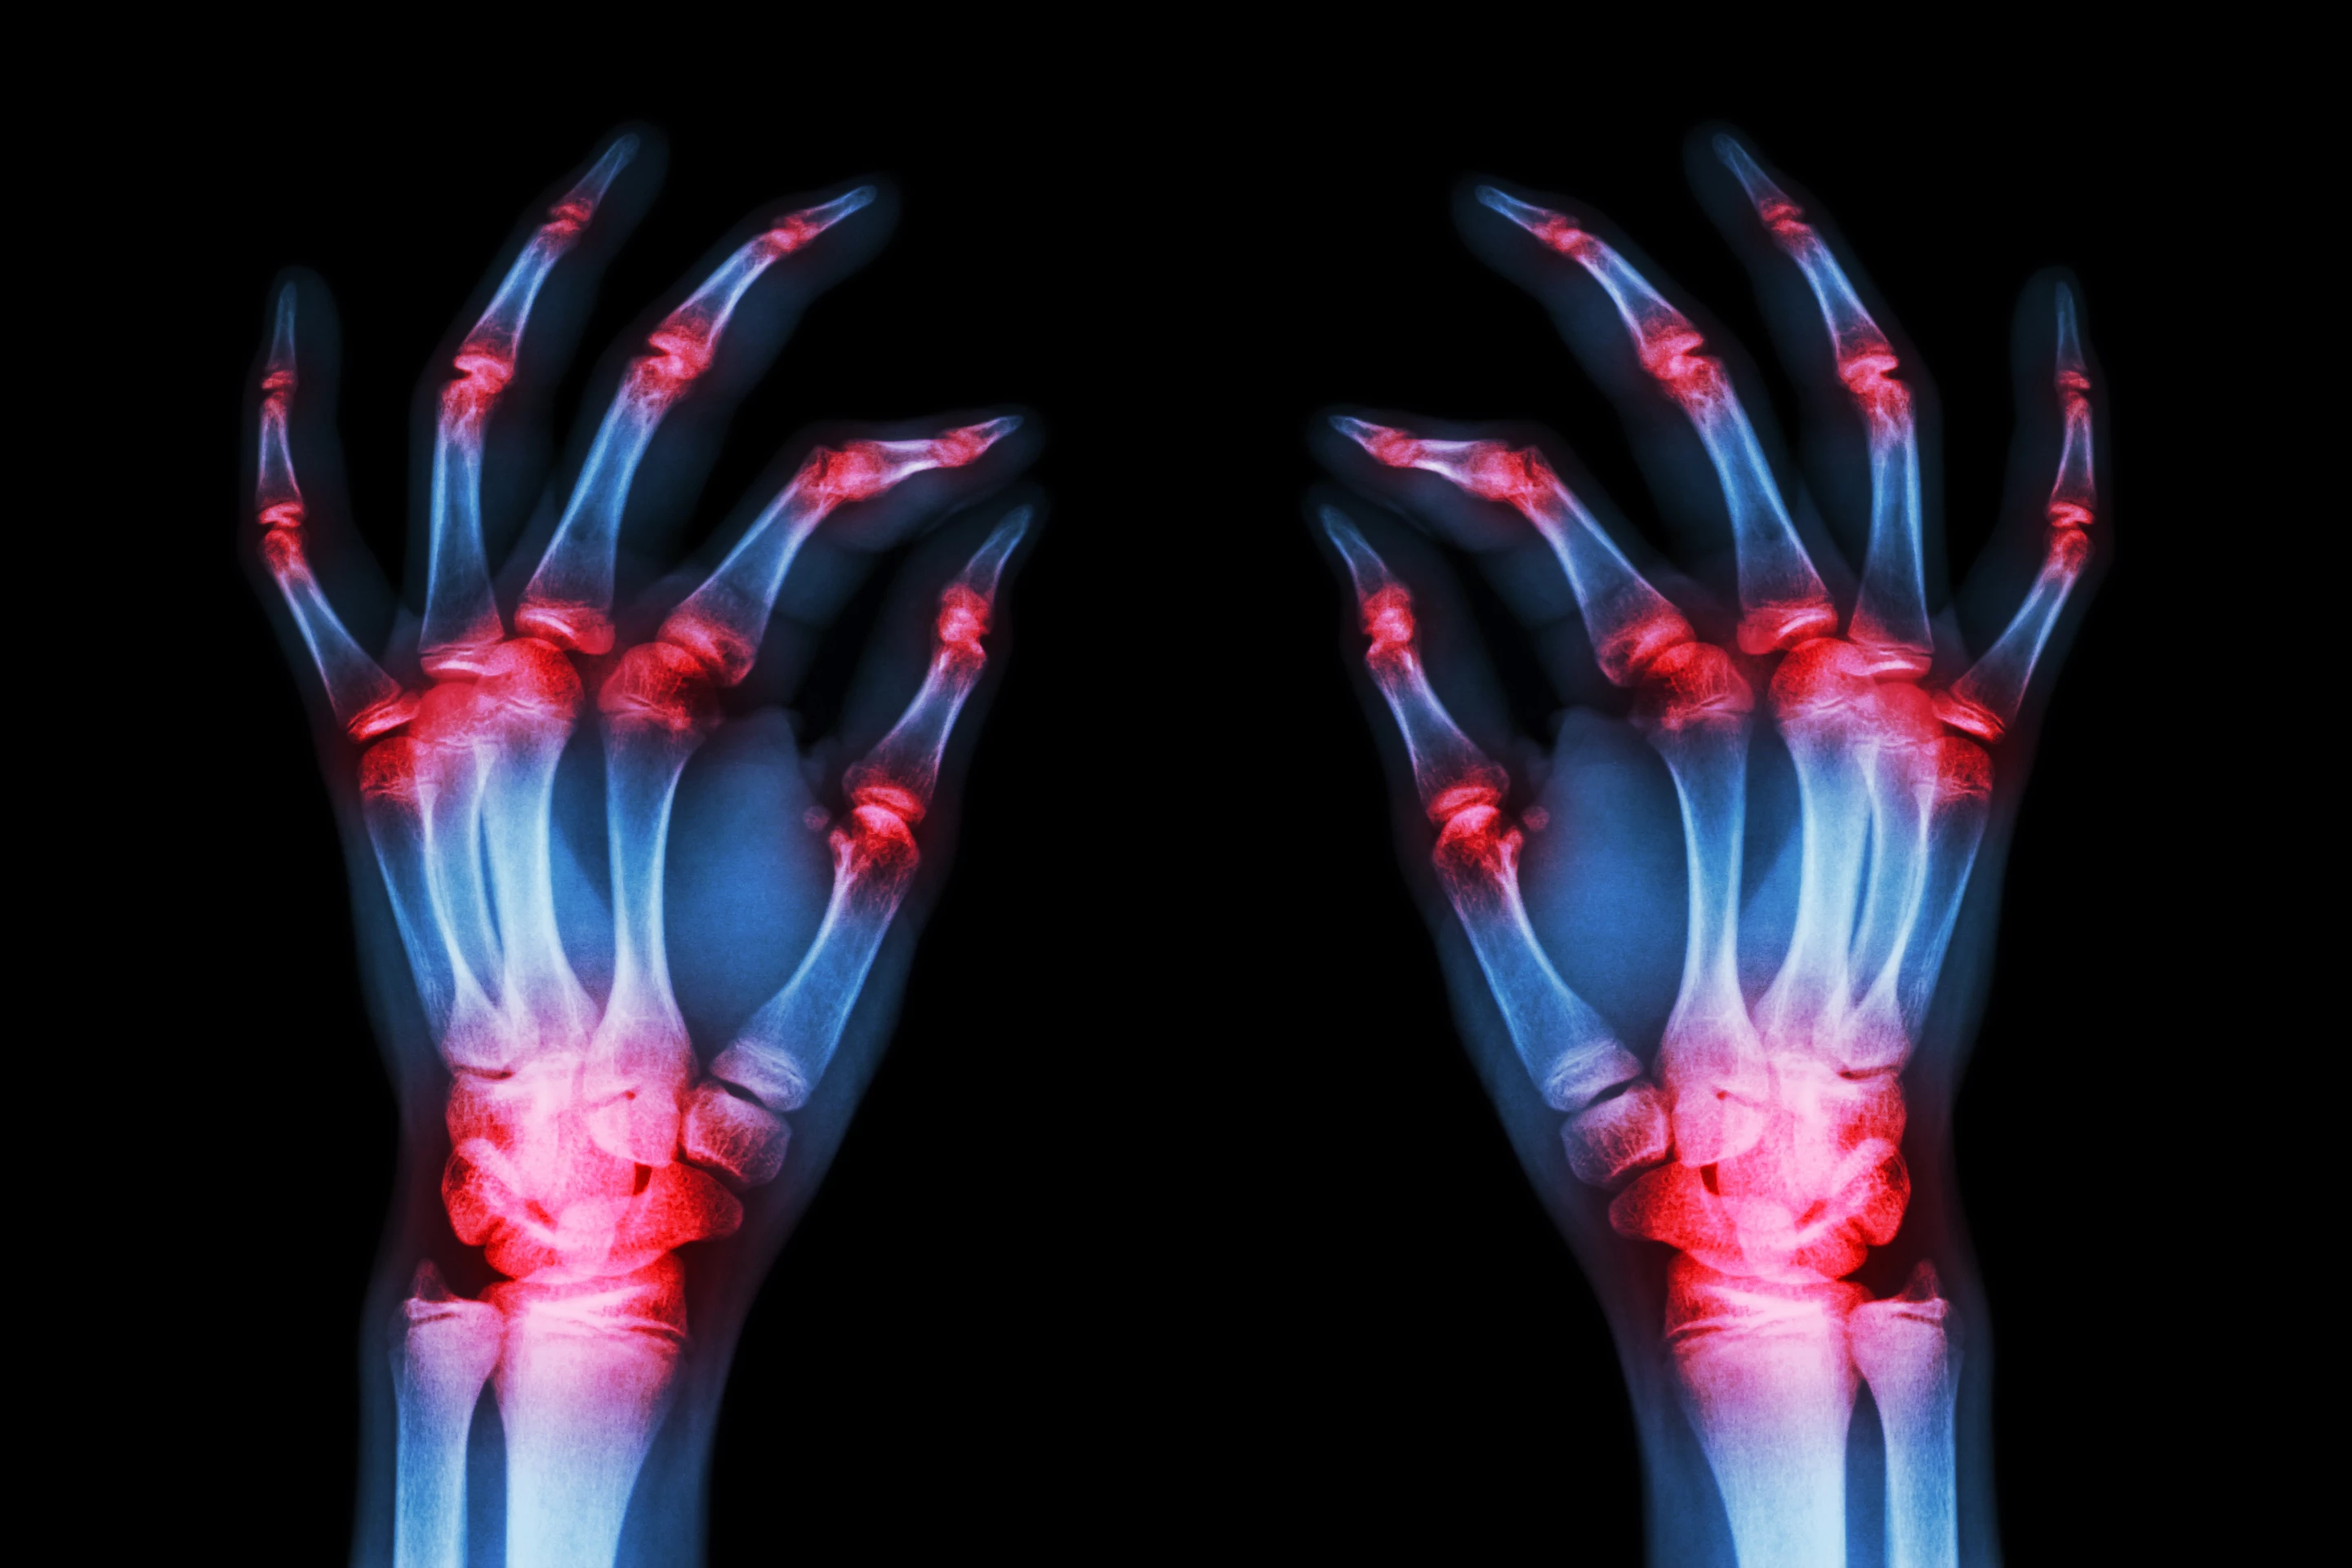

The research is still in preliminary stages but if further validated it could lead to new classes of drugs to treat rheumatoid arthritis

A team of researchers in the United States has discovered a novel mechanism in which a key protein drives the inflammatory damage associated with rheumatoid arthritis. The foundational finding is hoped to direct research toward entirely new pathways to treat this autoimmune disease affecting millions.

The new lab-based research focused on a type of human cell called synovial fibroblasts. These are the cells that line joints, and in cases of rheumatoid arthritis, inflammation in synovial fibroblasts is triggered by TNF-alpha.